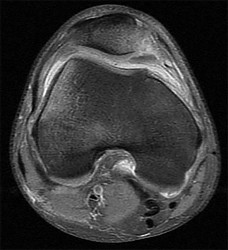

Question 11

A 9-year-old boy sustains a distal femur fracture. Radiographs demonstrate a fracture line propagating along the physis and exiting through the metaphysis, producing a small metaphyseal bone fragment (Thurston-Holland fragment). Based on the Salter-Harris classification, what type of fracture is this, and what is the typical expectation regarding growth arrest?

Explanation

A fracture that propagates through the physis and exits through the metaphysis (creating a Thurston-Holland fragment) is a Salter-Harris Type II fracture. It is the most common physeal fracture pattern. Because the germinal layers of the physis remain attached to the epiphysis, the general prognosis for growth is good. However, one must recognize that Type II fractures of the distal femur inherently carry a high risk of growth arrest (up to 40-50%) compared to other locations.